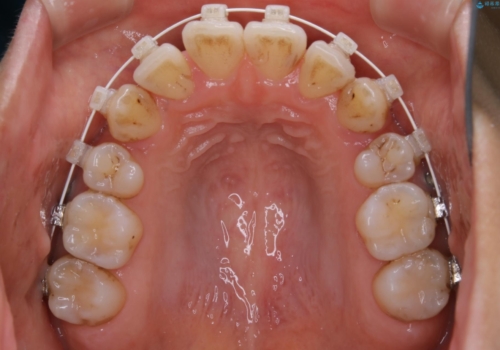

- 矯正装置

- ワイヤー(審美装置)

- 以前からコンプレックスだった八重歯の治療を主訴にご来院されました。

検査の結果、抜歯をすることでスペースを作って並べる方法が選択され、ワイヤー装置を用いた治療を開始することとなりました。

奥歯の上下のズレ等は軽度で、必要なスペースと抜歯により作られるスペースがほぼ等量だったため治療の単純化が計れ、大きな移動・見た目の劇的な変化に対して比較的早期での治療完了となりました。

叢生の度合いが重く、抜歯が必要なケース。八重歯の部分以外には大きな問題は認められなかったため、劇的変化が起こる治療でも比較的短期間で終了することができました。